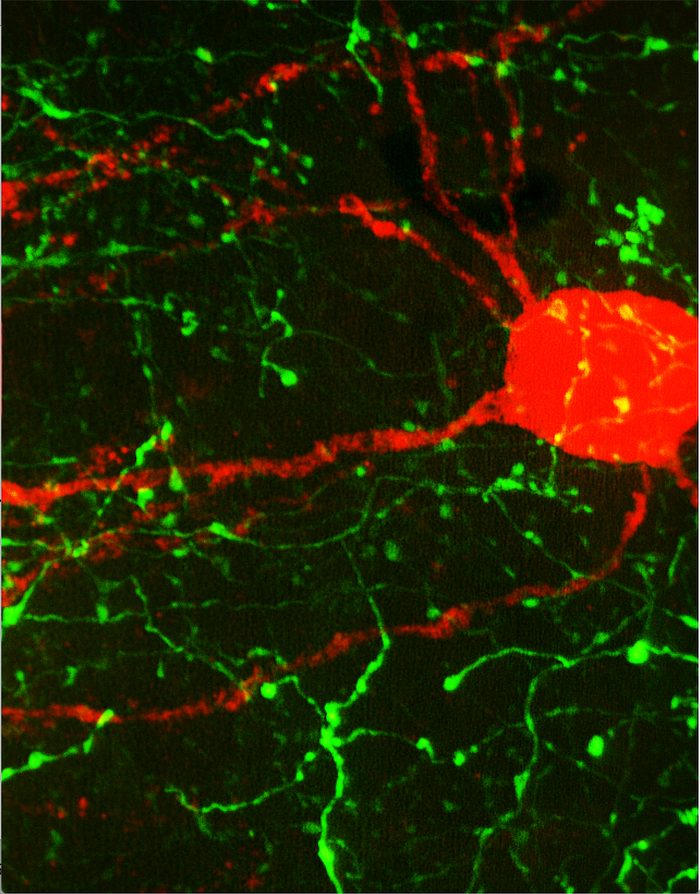

The researchers identified area 32 using neural tracers to visualize the connections between cognitive (DLPFC) and emotional (area 25) brain regions in rhesus monkeys. Their discovery helps us better understand what makes certain people more susceptible to depression — and can inform different treatment approaches.

In healthy brains, the DLPFC signals area 32 to balance area 25 activity, enabling emotional stability. Emotional balance goes haywire in mood disorders like depression, leading to unchecked negative emotions and an inability to break out of rumination. This runaway negative emotion is often caused by an overactive area 25. The researchers speculate that in individuals where area 32 has weaker connections with DLPFC and area 25, emotional regulation may be more difficult — perhaps rendering individuals vulnerable to depression. Furthermore, identifying and evaluating the strength of area 32’s connections with DLPFC and area 25 can help inform which treatment approach to take for people suffering from depression — ranging from cognitive behavior therapy, to medication, to deep brain stimulation.

So, what do these critical interactions between brain regions actually look like? The researchers take us into their lab for an inside-look: